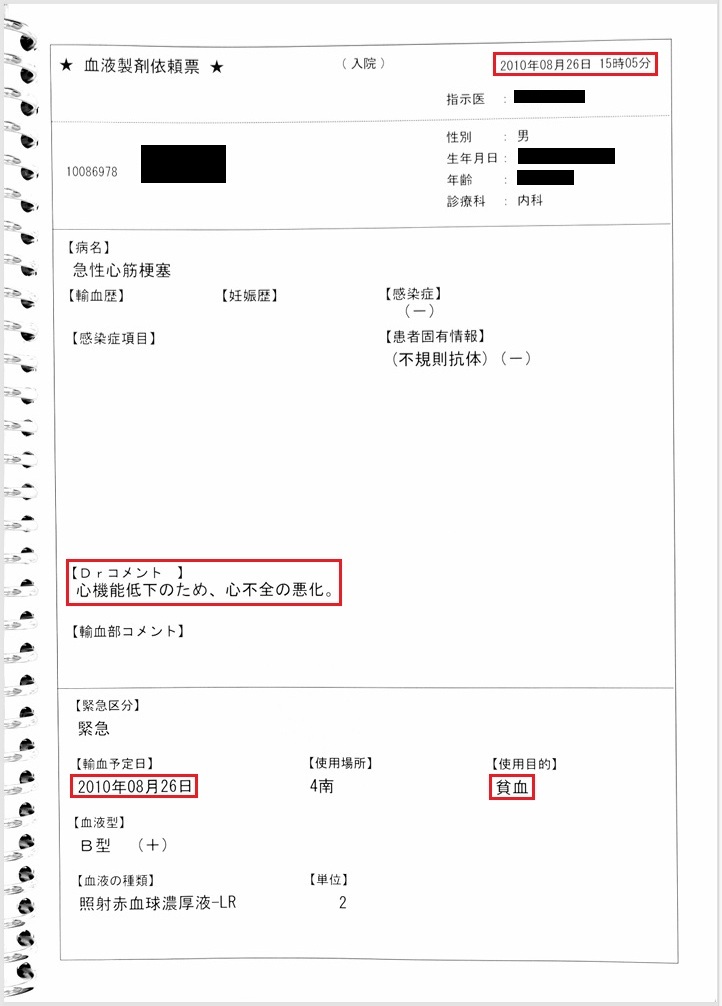

- 8月26日:Hb 11.1 g/dlで輸血開始

貧血にて輸血開始(カルテ・看護記録に記載あり)。しかし当日の血液検査ではHb 11.1 g/dlと貧血は軽度。 Hb 11.1 g/dlが本当であれば不適切診療。輸血が必要な状態であれば、Hb 11.1 g/dlは虚偽。

証拠:カルテ・看護記録・血液検査の抜粋